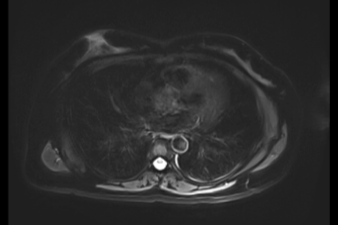

控糖不力,并发症悄然而至——影像学评估心、脑、肾、足风险